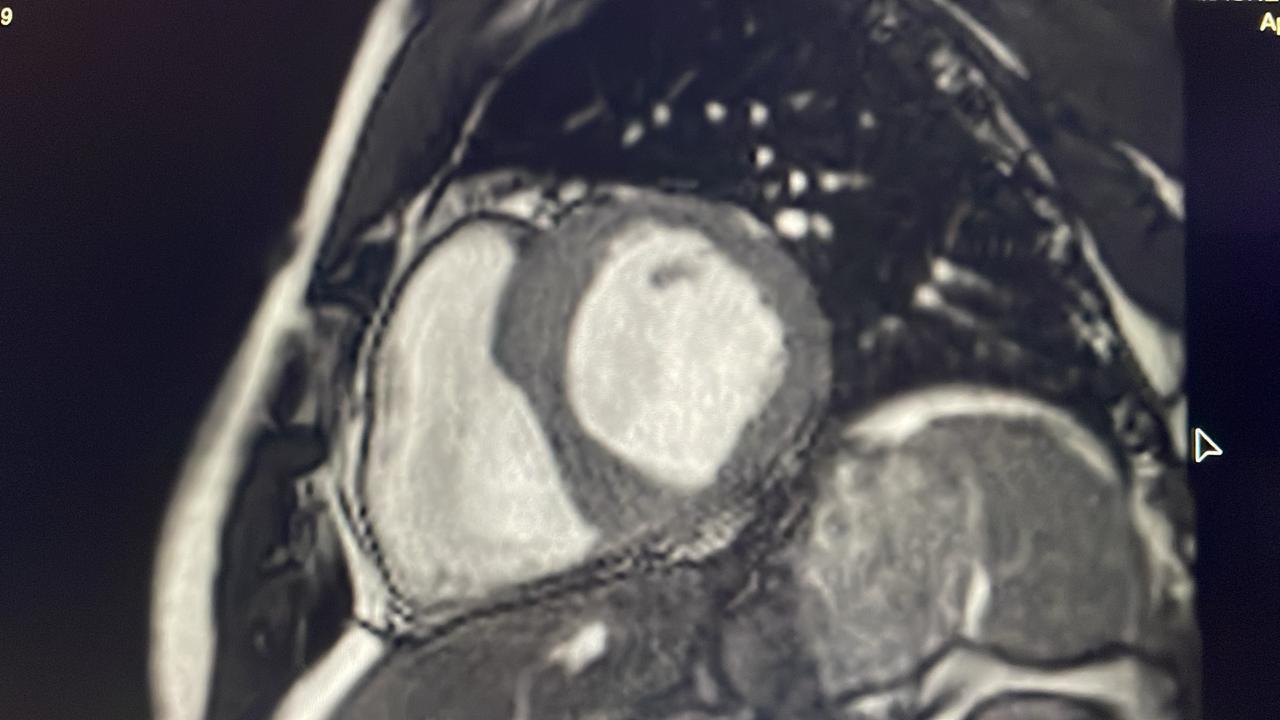

Hook Sign